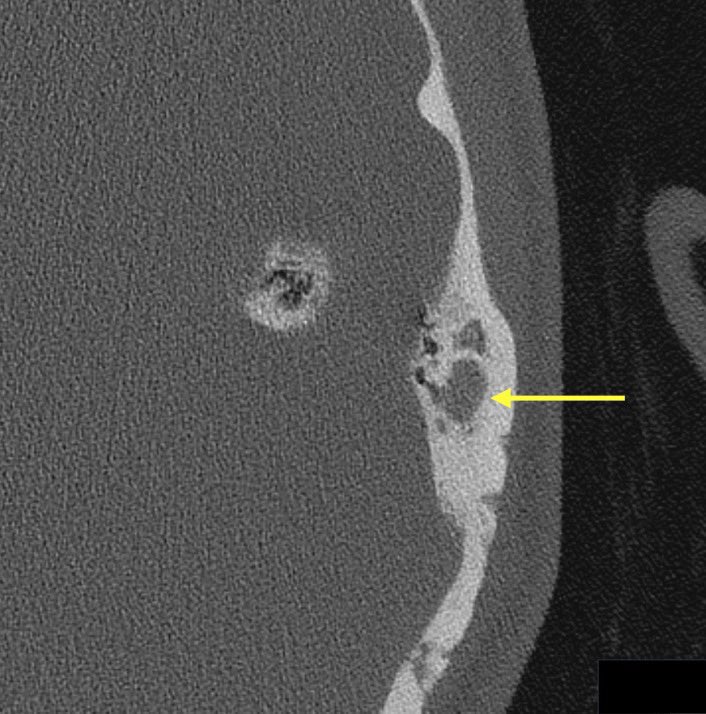

🔷SIGMOID SINUS WALL ANOMALIES

1️⃣Sigmoid plate dehiscence

2️⃣Sigmoid sinus diverticulum

🔹Sigmoid plate dehiscence: Thinning or absence of the normal cortical bone covering the sigmoid sinus resulting in direct contact of the venous sinus wall with mastoid air cells

🔹Sigmoid sinus diverticulum: Lateral outpouching of the transverse sigmoid sinus junction with intrusion into the adjacent bone

💡 Sigmoid plate dehiscence w/ or w/o diverticulum is one of the most common imaging abnormalities at CT for pulsatile tinnitus (up to 40%). These findings are more prevalent in patients with TSS and IIH